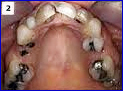

There are several types of bridges. You and your dentist will discuss the best options for your particular case. The “traditional bridge” is the most popular type and is usually made of porcelain fused to metal. Porcelain fixed bridges are most popular because they resemble your natural teeth. This type of bridge consists to two crowns that go over two anchoring teeth (abutment teeth) and are attached to pontics (artificial teeth), filling the gap created by one or more missing teeth.

We will prescribe a bridge when one or more teeth are missing and there are healthy teeth on both sides of the open space. Bridges can be made from three types of material, solid gold for reliable long wear, porcelain fused to a gold base for strength and beauty, and high-strength metal-free porcelain for optimum cosmetic results. With proper care, your new bridge will increase your overall health and instill confidence for years to come.